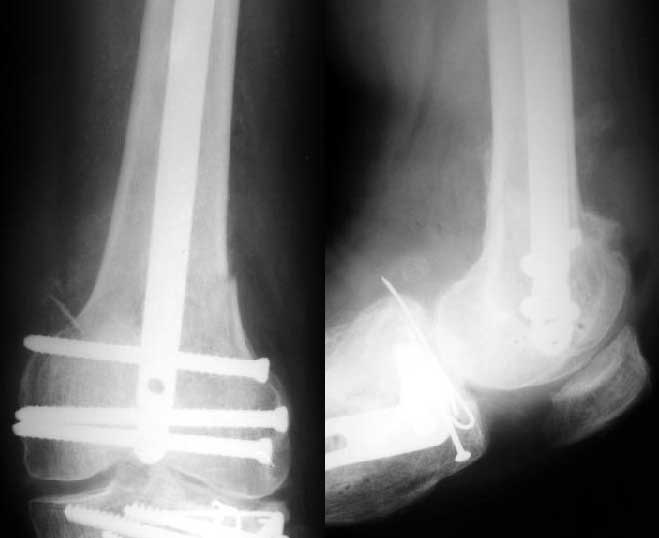

1

2

de> you think you are using antigrade nails for some very low

de> fractures including some intercondylar fractures.

Exactly. It seems the option looks underestimated.

de> Do ou have a reference supporting antigrade nailing in such

de> occasio in favour of other choices eg DCS, Supracondylar nail,

No, i haven't seen such comparisons. However some advantages of closed antegrade nailing vs conventional plating looks self-evident like no site opeining, no bone skeletization, less blood loss, no need for autografting... If you or other colleagues can help me with the references it would be greatly appreciated. I would be interested also to compare ante- vs retrograde nailing for the localization.

de> And perhaps you could show us also some of your results ,

de> that is (follow up) not immediate postop x rays.

I attached an example of C2 fracture with result of the same technique in 5 months.